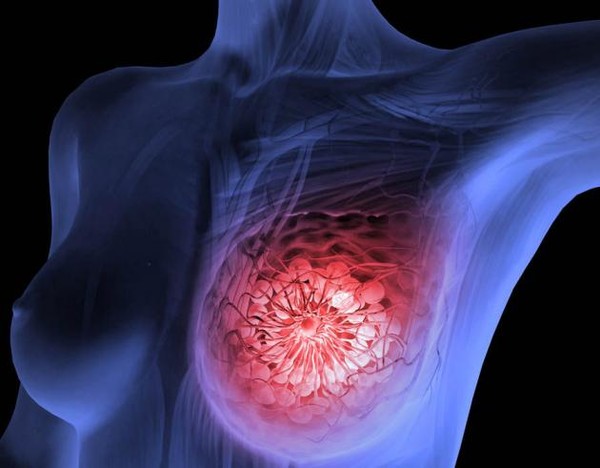

유방암은 여성에게 가장 흔한 암 중 하나로, 조기 발견과 치료가 생존율에 큰 영향을 미칩니다. 이번 포스팅에서는 유방암 초기증상, 2기 생존율, 수술 후 회복기간에 대해 자세히 알아보겠습니다.

유방암은 조기 발견과 치료로 높은 생존율을 기대할 수 있는 질환입니다. 초기증상을 놓치지 않고, 정기 검진과 생활 관리에 힘쓴다면 건강한 삶을 이어갈 수 있습니다.

유방암이 의심되거나 관련 증상이 나타난다면 망설이지 말고 전문의 상담을 받아보세요. 건강을 지키는 가장 중요한 첫걸음은 조기 발견입니다!